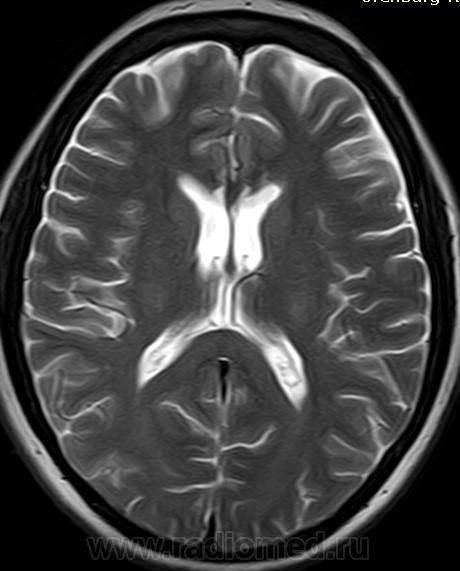

МРТ головного мозга, мозолистое тело

Женщина, около 40 лет. Заболела остро несколько месяцев назад, по КТ было выставлено субарахноидальное кровоизлияние. Снимки, как обычно, остались домаangry.

В настоящее время невролога насторожили признаки поражения мозолистого тела - апраксия. Для исключения опухоли мозолистого тела направлена на МРТ.

Я думаю инфаркты в мозолистом теле.

Да так и есть! У меня возникла мысль о Маркиафава-Беньями. Но никакого анамнеза. Женщина довольно молодая, сохранная, социально адаптирована. Потом выяснилось, что КТ делали в начале заболевания дважды с интервалом в несколько дней. Первый раз написали субарахноидальное кровоизлияние, второй раз внутрижелудочковое кровоизлияние в стадии рассасывания. Это меня озадачило. Я потребовала снимки, и получила их. Что скажете?

Снимки мелковаты, но кажется видно, что это свежий инфаркт в мозолистом теле. Кровоизлияний нет. При обследовании у больной выявили наследственную тромбофилию.

да, мозолистое и выше пострадавшее, на Т2 видно

Мало снимков и очень плохо видно. Но здесь отмечается небольшая дефармация боковых желудочков, кистозные участки в мозолистом теле, возможно, с учетом предыдущий исследований и расценивать нужно, как постишемические изменения.

Именно так я и расценила: инфаркт в мозолистом теле. На КТ острый инфаркт - отек и понижение плотности мозолистого тела, на МРТ последствия инфаркта.

Почему не делали FLAIR и Т2*? На Т2 явно видно понижение уровня сигнала - Вам не кажется, что это геморрагические изменения?

Острый инфаркт зафиксирован на КТ+анамнез, острое начало заболевания.

На МРТ через несколько месяцев постинфарктные изменения с признаками геморрагической трансформации в зоне некроза.

Мне не очень верится в то, что почти все мозолистое тело, за исключением валика, сразу подверглось инфаркту. Для этого нужна симметричная окклюзия обеих перикаллезных артерий. Откуда она взялась, особенно учитывая отсутствие "цисциркуляторного" анамнеза?

Я бы все-таки поставил на первое место болезнь Мархиафавы-Биньями. Вот, нашел статью про разные поражения мозолистого тела: http://www.ajronline.org/content/179/1/251.full. Выдрал оттуда картинку, на ней хроническая стадия болезни. Видно то же самое: атрофия клюва и ствола мозолистого тела, валик сохранен.

Насчет Маркиафавы, первая мысль была о нем. Но алкогольного анамнеза нет. Не помню писала я или нет, у больной при обследовании выявили наследственную тробофилию.